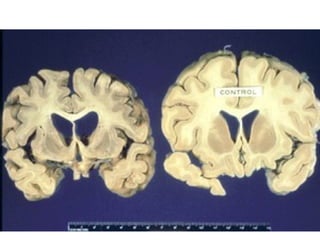

• L’ensemble de ces maladies se

caractérise par une dégénérescence du

système nerveux central (cerveau et

moelle épinière) liée à la propagation ou

multiplication des prions chez l’hôte

infecté.

• L’ensemble deces maladies se caractérise par une dégénérescence du système nerveux central (cerveau et moelle épinière) liée à la propagation ou multiplication des prions chez l’hôte infecté.